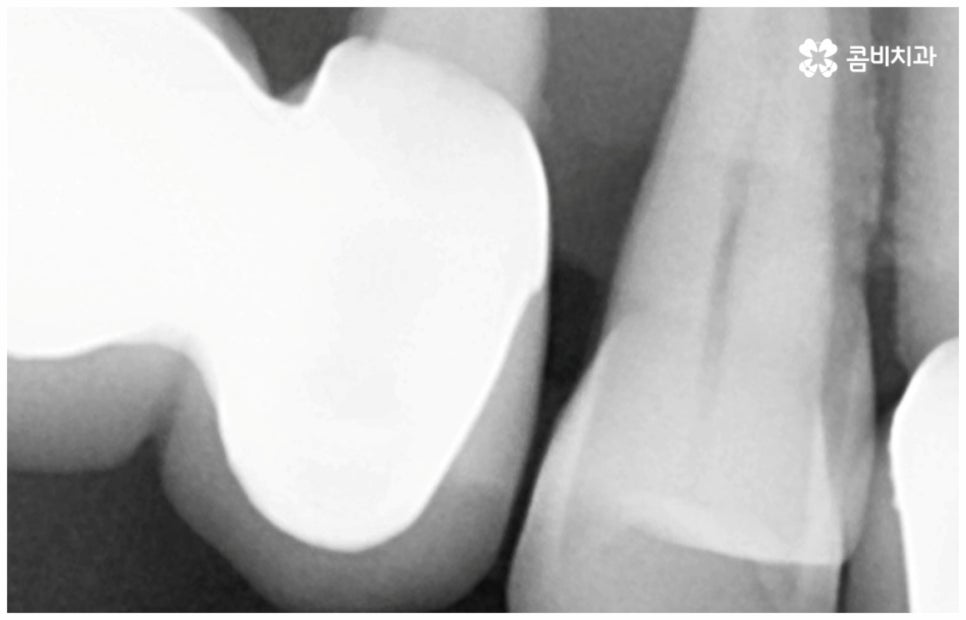

그러나 노화나 구강 질환을 원인으로 한 경우에는 식립 절차가 좀 더 복잡해 질 수 있는데요. 잇몸병을 예로 들어 생각해 보면 자연스러운 노화 및 관리 소홀로 인해 치아 주변 조직 (잇몸, 치주인대, 치조골 등) 에 염증 반응이 생기는 병인 치주 질환이 많이 심해졌을 때 상황에 따라 해당 자연 치아를 살리지 못하고 발치를 해야할 수도 있는 거예요. 이렇게 치주질환을 이유로 임플란트 식립을 진행할 때에는 식립 성공률을 높이고 임플란트수명 을 늘리기 위해 먼저 치주질환 치료를 선행해 줘야 하며, 환자분들의 상황에 따라 뼈이식 또는 상악동 거상술을 통해 잇몸뼈를 보충해 줘야 할 수도 있어요. 치조골이 이미 많이 녹아 있거나 병증이 극심하다면 임플란트 식립 난이도가 매우 높아지거나 때로는 불가능해 질 수 있기 때문에 다양한 임상 경험을 통해 풍부한 노하우를 가지고 있는 의료진에게 진단 및 치료를 받는 것이 굉장히 중요한 포인트라고 할 수 있습니다.